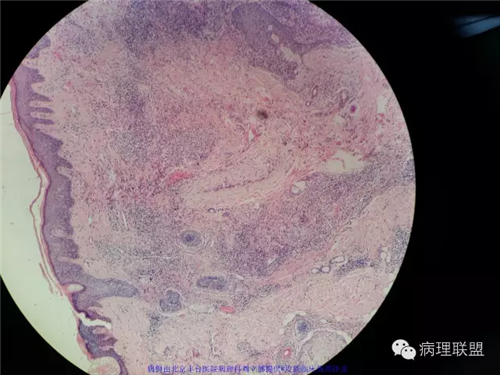

皮肤血管肉瘤

男性,29岁,左眉弓红色丘疹,直径0.5cm。病史:患者病程2个月

(注:病例由北京丰台医院病理科刘立娜提供 致谢!)